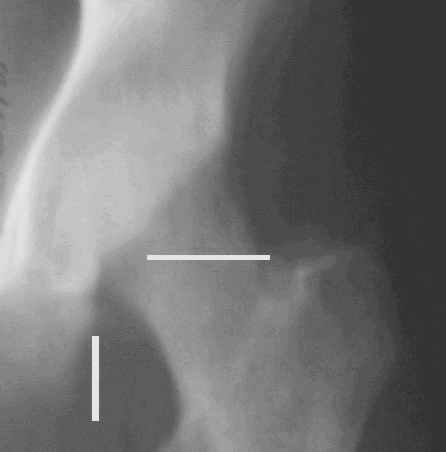

Уважаемые коллеги! Заканчивая обследование больного с переломо-вывихом бедра сделал ему обычные R-томограммы. Кажется удалось "поймать" и отломок и донорское место. Мои выводы - в скиаграмме. Считаю, что это передне-нижний фрагмент головки, образовавшийся вследствии отрывного перелома. На томограммах отломок обозначаю длинной стрелкой, а место откуда он оторвался - более короткой. Учитывая тот факт, что его размеры по КТ 25 х 15 мм считаю, что его фиксация на место необходима для профилактики артроза, что при 16-ти летнем возрасте пациента важно в плане максимального отодвигания эндопротезирования. Планирую оперировать его 24.05.05 г. Результаты представлю.

Несколько соображений к "картинкам". На прямом снимке и КТ-томограммах все типичные линии вертлужной впадины: крыша, передняя стенка, задняя стенка - сохранены. На КТ-сканах 6 и 7 появляется фрагментация головки. С учетом R-томограмм отломок расположен спереди-снизу, а не сзади-сверху от сустава, как написано в описании КТ.